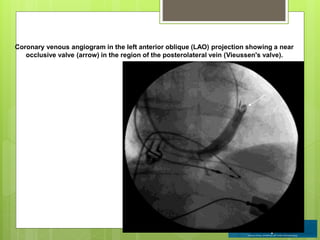

Coronary venous angiogram in the left anterior oblique (LAO) projection showing a near

occlusive valve (arrow) in the region of the posterolateral vein (Vieussen's valve).

The MCV isa very consistent tributary of the CS present in nearly all hearts.

Coronary venous angiogramin the left anterior oblique (LAO) projection showing a near occlusive valve (arrow) in the region of the posterolateral vein (Vieussen's valve).